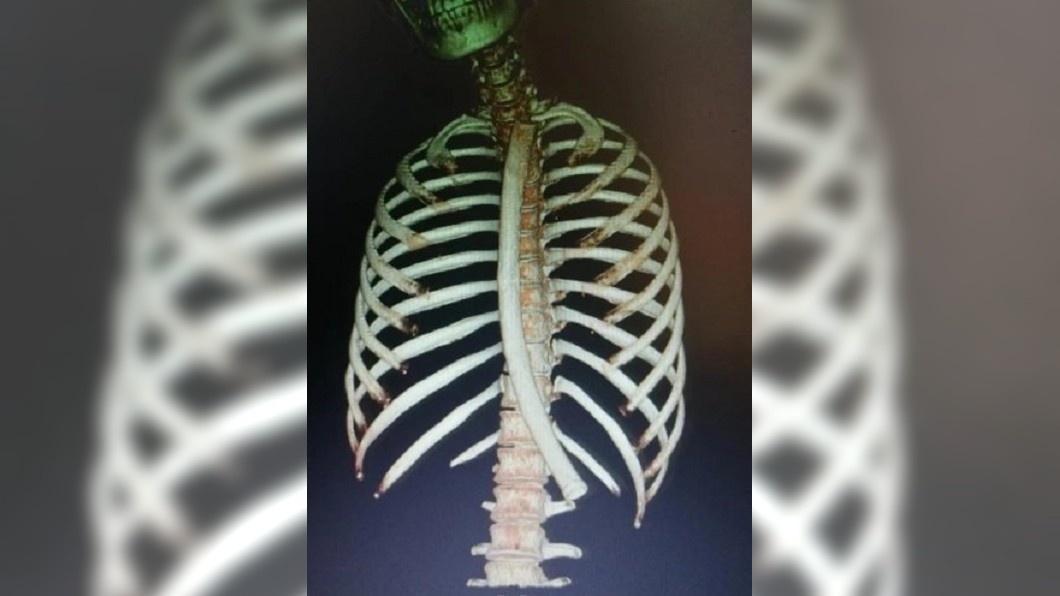

Kết quả X-quang cho thấy hình ảnh chiếc ống hút dài từ đốt sống dưới cổ đến đáy dạ dày. Các bác sĩ đã tiến hành thủ thuật gắp chiếc ống ra ngoài ngay lập tức. Tuy nhiên, dị vật không phải ống hút trà sữa mà là loại ống kích nôn được bán tràn lan trên các trang bán hàng trực tuyến tại Trung Quốc.

Ống kích nôn trong thực quản của bệnh nhân. Ảnh: Tvbs.